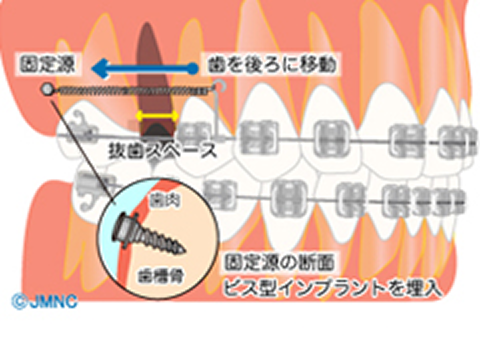

インプラント矯正

『インプラント矯正』は、アンカーインプラントというごく小さなインプラントを一時的に顎の骨に埋め込み、それを歯を動かすための固定源にする治療法です。治療が完了したら、インプラントを取り除きます。

ブラケットとワイヤーを使用する一般的な装置の場合、ワイヤーで連結した歯と歯が引っ張り合って歯を移動させますが、これだと連結したそれぞれの歯が移動してしまい、引っ張る力が安定しません。

しかしインプラント矯正は、矯正用のインプラントを支点とするため、固定源が動いてしまうことなく効率的に歯を動かすことができます。それが治療期間の短縮につながります。

また、インプラントの埋入位置によっては、歯を前後・左右・上下と立体的に動かすことが可能です。

ただし、インプラント埋入のための外科手術が必要となり、埋め込んだ後は、その周りの衛生状態に気を配っていないと感染を起こすことがあるので、注意が必要です。

後方移動では矯正用のインプラントを使用し、それを固定源として歯を動かすので、従来のように奥歯が前に移動することなく治療を行うことができます。